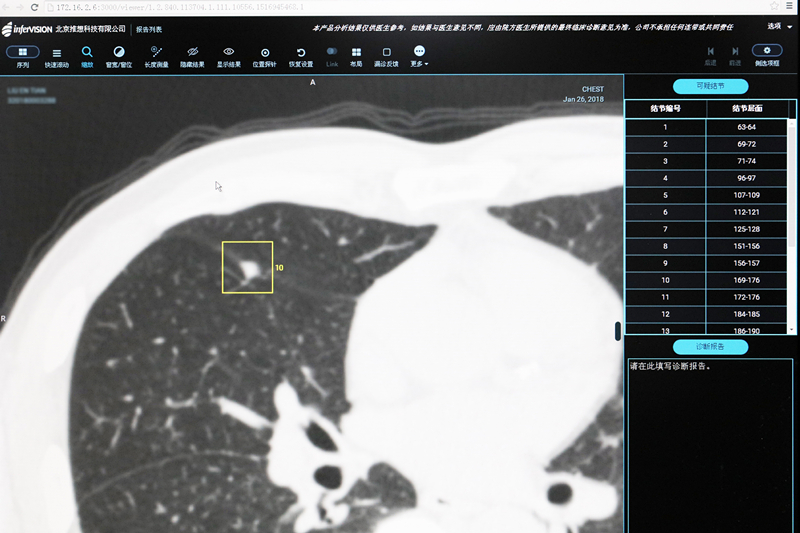

阿尔法狗有多“聪明”,想必大家都知道。近日,烟台山医院在肺结节CT筛查时就用上了人工智能技术,“CT界的阿尔法狗”在烟台山医院CTMR室“上岗”,它是最智能的“CT室医生”,它可以在5秒之内读完患者的胸部CT片,并能将可疑部位进行自动标注,它对肺结节的发现辨识率高达90%,医生读片的结果也可以请它进行进一步核实。它与CT室医生携手作战让肺结节筛查更加高效、精准。

现在,“CT界的阿尔法狗”“上岗”,让肺结节筛查可以更快、更准。它的名字是“人工智能肺结节筛查系统”,英文名字为“AI-CT Chest”,它是“人工智能+医疗”界的翘楚,在烟台山医院“上岗”前,它已学习过40多万例专业医师标记的胸片和胸部CT阅片信息,并深深地印在自己的“脑海”里。在阅片经验方面,可以称得上是“老司机”,在阅片时,它可以模拟人的思维,阅完一个肺结节筛查胸部CT片,只需要5秒钟,并能标注出可疑结节的位置,以供CT室医生进行进一步核实。“此外,我们医生阅读完的片子,也可以请它进行进一步验证,以降低肺结节的误诊率和漏诊率。”张国伟表示,“CT界的阿尔法狗”不仅是一个工具,更是CT室医生的亲密“战友”,他们携手作战,让肺结节筛查更加高效、精准,有助于肺癌的早发现、早治疗,进而能更好地服务患者。